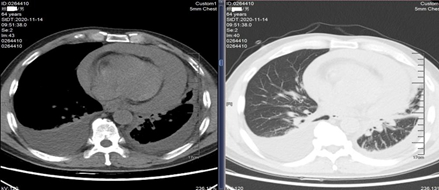

引流胸水及心包积液,血常规检测发现患者血红蛋白达到90g/L。

穿刺位置及心包积液血常规检测结果

将心包积液进行病理检测,可见腺癌细胞,初步判断为疑似腺癌超进展(即肿瘤经治疗后不但没缩小,反倒以更快的速度增长)。

施敏骅教授:对于该病例,可能是出现了心包出血的问题,后续的双侧胸腔积液的产生,可能也与心包内毛细血管静水压的增高有关,心包积液血红蛋白已经超过外周血内血红蛋白的一半以上数量,可能是因为肿瘤的心包转移和抗血管药物作用,导致的心包出血。

一个月以后复查的CT结果显示,患者好转,心包积液消失,两侧胸水消失,病灶仍然存在。

复查CT对比图